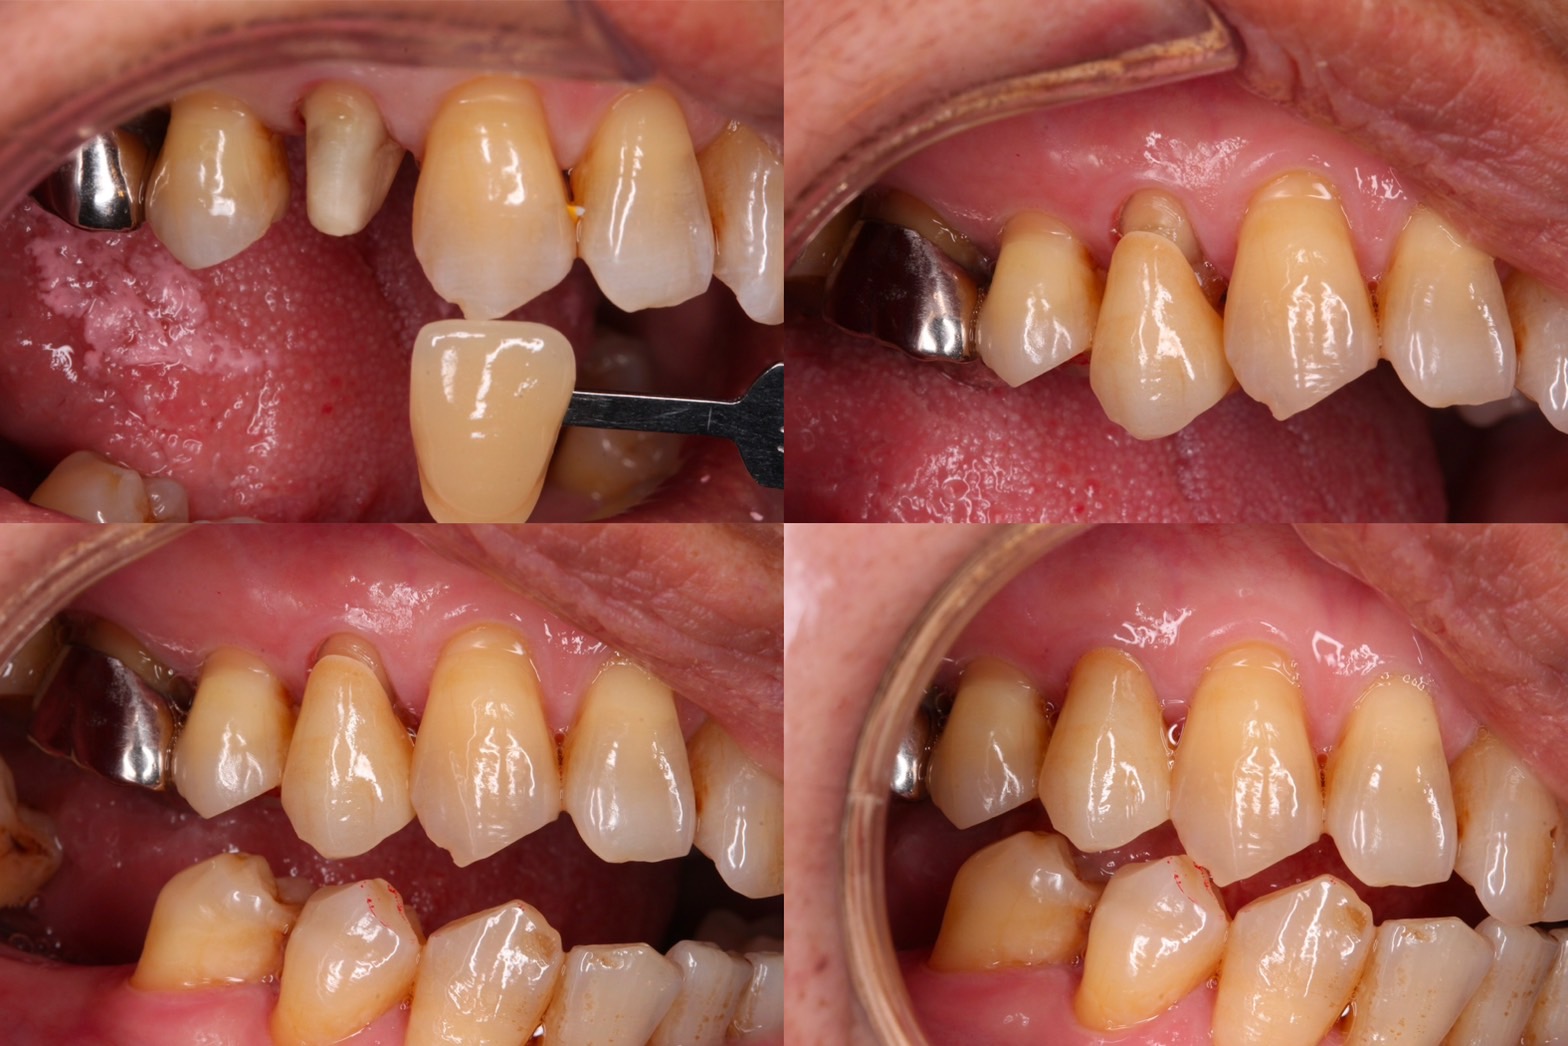

固定式假牙種類1:單顆牙冠

用於單顆牙齒需要修復的情況,可能需要搭配牙釘。牙冠的材質選擇很多,常見如金屬假牙、金屬燒附瓷牙、全瓷冠、全鋯冠等。

固定式假牙種類3:陶瓷貼片

常見的材質是由全陶瓷製成,屬於固定式的補綴物(修復物),較常用於前牙。將貼片黏著在牙齒上,用以修補缺損,例如反覆填補造成不好看的樹脂填補物染色的牙齒,或是因外力撞擊造成的斷裂和大範圍面積的蛀牙,陶瓷貼片常能達到最好的美觀需求。